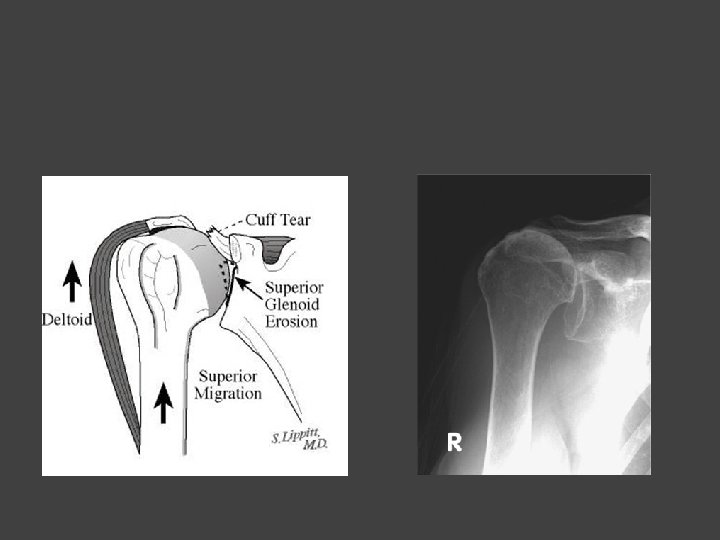

Expanding Use of RSA • FDA approved for use in 2003 • Used since the early 1990’s in Europe • Initially approved for treatment of cuff tear arthropathy